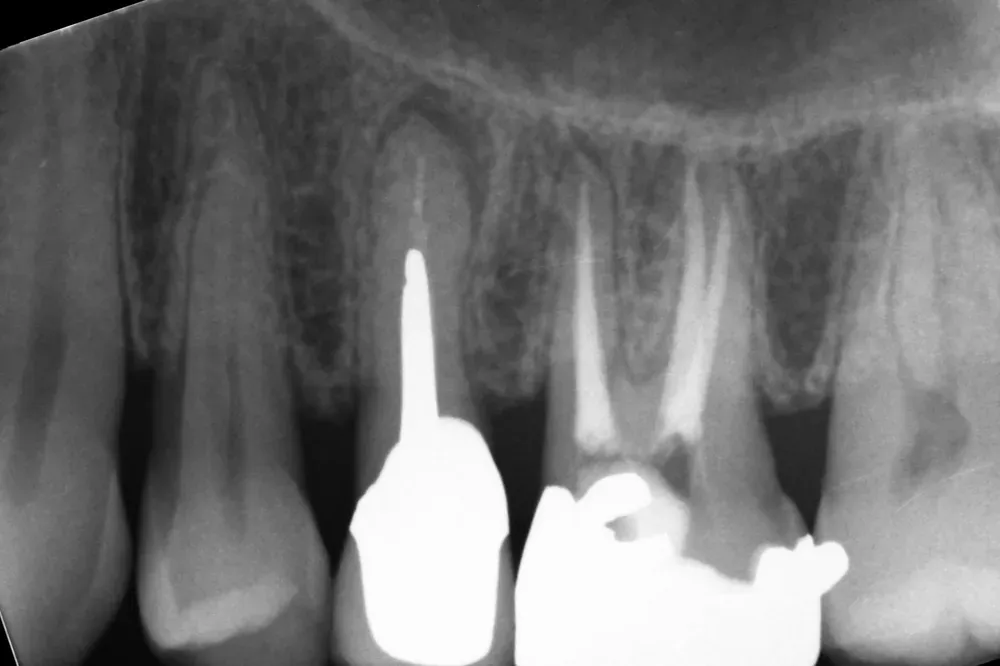

Gli esami strumentali permettono di simulare, ancora prima dell’intervento chirurgico, la posizione tridimensionale degli impianti per assicurarsi che non vadano a interferire con strutture anatomiche nobili come il nervo alveolare inferiore, il seno mascellare o le radici dei denti adiacenti che devono essere preservate.

Personalmente, amo scegliere il numero e le misure degli impianti in base alle caratteristiche anatomiche del singolo paziente, piuttosto che affidarmi a protocolli troppo rigidi e standardizzati. Sempre nell’ottica della rigenerazione su misura, ritengo che ogni caso debba essere studiato individualmente per ottimizzare il risultato finale.

Le immagini radiografiche che seguono testimoniano alcune delle tante soluzioni tecniche che ho utilizzato per le arcate a carico immediato nel corso della mia carriera. Ogni caso presenta sfide diverse e richiede un approccio personalizzato.